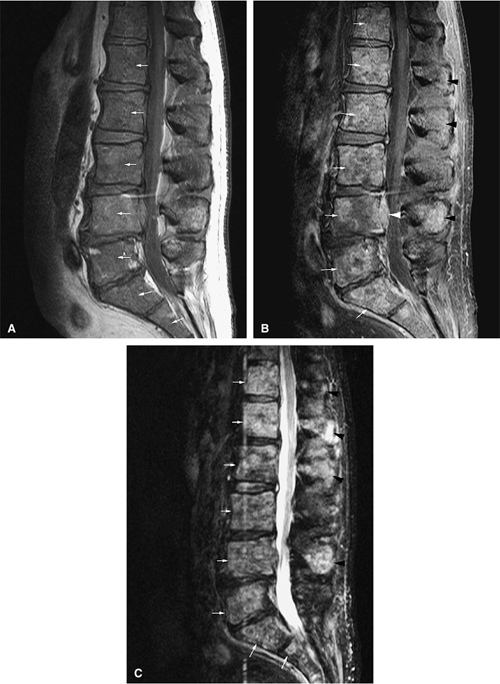

FIGURE 13.51 ● Diffuse marrow replacement with an epidural soft-tissue mass in a patient with multiple myeloma. (A) Sagittal T1-weighted image shows diffuse marrow replacement of the lumbar spine. The large epidural soft-tissue lesion causes a mass effect on the thecal sac (arrow). Myelomatous marrow infiltration is darker than the adjacent intervertebral disks. (B) Enhancement of the soft-tissue mass is shown on a sagittal fat-suppressed T1-weighted image after intravenous administration of gadolinium (arrow). (C) Diffuse marrow replacement is not well seen on the corresponding sagittal T2-weighted image.

|